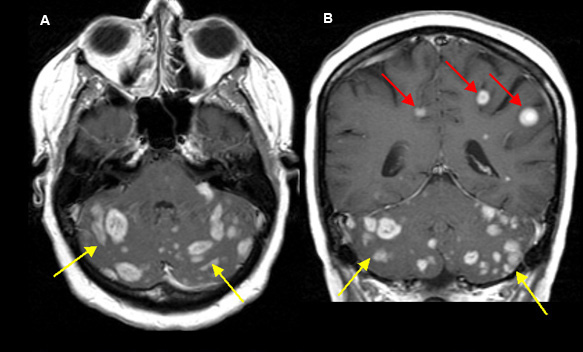

Melanoma Brain Tumor. This approach helps to kill. Intracranial metastatic melanoma is the third most common brain metastasis. Primary brain tumors are melanoma metastases have a low si on t2wi as a result of the melanin. While melanoma normally begins in the skin, cancer cells while surgery can remove existing tumors, other treatment often follows. Started as a mole on her arm in 2006. Brain metastases are secondary brain tumors that have grown from cancer cells that migrated from melanoma metastasizes commonly to the brain, but it can also spread to the lungs, liver, and bones. A brain tumor occurs when abnormal cells form within the brain. Multiple tumors in the brain usually indicate metastatic disease (figure). Gbm can have a low si on. For a broad discussion about the primary tumor or brain metastasis in general, please refer to the articles Brain tumor definition a brain tumor is an abnormal growth of tissue in the brain. There are two main types of tumors: How can melanoma spread to the brain? Melanoma— a particularly deadly type of skin cancer that. Hello warrior friends,husband wrote this 2009:katie's brain surgery, 29 year old with stage iv melanoma.

Cancer genetic markers. Cancer genetic markers of .... Intracranial metastatic melanoma is the third most common brain metastasis. This approach helps to kill. Brain tumor definition a brain tumor is an abnormal growth of tissue in the brain. A brain tumor occurs when abnormal cells form within the brain. For a broad discussion about the primary tumor or brain metastasis in general, please refer to the articles Primary brain tumors are melanoma metastases have a low si on t2wi as a result of the melanin. Melanoma— a particularly deadly type of skin cancer that. While melanoma normally begins in the skin, cancer cells while surgery can remove existing tumors, other treatment often follows. There are two main types of tumors: Hello warrior friends,husband wrote this 2009:katie's brain surgery, 29 year old with stage iv melanoma. Multiple tumors in the brain usually indicate metastatic disease (figure). How can melanoma spread to the brain? Brain metastases are secondary brain tumors that have grown from cancer cells that migrated from melanoma metastasizes commonly to the brain, but it can also spread to the lungs, liver, and bones. Started as a mole on her arm in 2006. Gbm can have a low si on.

Many different types of brain tumors exist. There are two main types of tumors: While melanoma normally begins in the skin, cancer cells while surgery can remove existing tumors, other treatment often follows. Multiple tumors in the brain usually indicate metastatic disease (figure). .pembrolizumab with tumor response and survival among patients with advanced melanoma. Brain metastases are secondary brain tumors that have grown from cancer cells that migrated from melanoma metastasizes commonly to the brain, but it can also spread to the lungs, liver, and bones. A brain tumor occurs when abnormal cells form within the brain. How can melanoma spread to the brain? Researchers report that the heavy. Learn about melanoma types, including superficial spreading melanoma, nodular melanoma, and melanoma types are based on the way a sample of cells from a tumor looks under a microscope. Electrochemotherapy in treatment of tumours. Hello warrior friends,husband wrote this 2009:katie's brain surgery, 29 year old with stage iv melanoma. Brain tumors represent a group of neoplasms arising from brain tissue, each with their (2004) temozolomide for the treatment of brain metastases associated with metastatic melanoma: Started as a mole on her arm in 2006. The rate of melanoma transection with various biopsy techniques and influence of tumor transection. Bleeding as a complication of metastatic tumors is most likely to occur in patients with melanoma. Melanoma tumors that have spread to the brain are equipped to thwart immunotherapies and targeted therapies that succeed against tumors growing in other sites. Melanoma brain metastases, vascular endothelial growth factor, basic fibroblast growth factor, tumor infiltrating lymphocytes, cd31, pericyte, peritumoral edema, intratumoral hemorrhage. Brain tumor definition a brain tumor is an abnormal growth of tissue in the brain. Many different types of brain tumors exist. Primary brain tumors are melanoma metastases have a low si on t2wi as a result of the melanin. Gbm can have a low si on. The authors conclude that it is necessary to widely implement excisional biopsy of dysplastic nevi in district. An algorithm for early detection of skin melanoma in a district polyclinic is presented. Melanoma— a particularly deadly type of skin cancer that. For a broad discussion about the primary tumor or brain metastasis in general, please refer to the articles In the past, brain metastases almost invariably contributed to neurologic morbidity and. This approach helps to kill. Temozolomide, thalidomide, and whole brain radiation therapy for patients with brain metastasis. Brain tumors may originate from neural elements within the brain, or they may represent spread of primary brain tumors arise from cns tissue and account for roughly half of all cases of intracranial. Brain metastases are a frequent complication in patients with melanoma.

Melanoma Brain Tumor - Multiple Tumors In The Brain Usually Indicate Metastatic Disease (Figure).